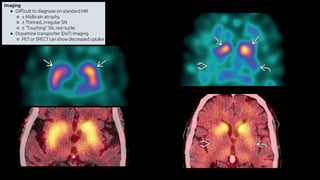

Doença de Parkinson

• Doença neurodegenerativa multissistêmica

• Parkinsonismo: Tremores, bradicinesia e rigidez

• 75% Doença de Parkinson

• Parkinson + demência = Demência da doença de Parkinson

• Parkinson + outros = Parkinson Plus

• Clínica

• Desordem neurodegenerativa

• Histopatologia

• Doença de corpos de Lewy

• Imunohistoquímica

• Sinucleinopatia

Introdução

• Etiologia

• Degeneração de neurônios dopaminérgicos (60%)

• Redução da dopamina no corpo estriado (80%)

• Idade

• Genética

• Patologia

• Atrofia mesencéfalo, com formato em “borboleta”

• Despigmentação da substância nigra

• Presença de corpúsculos de Lewy

• Tratamento

• Levodopa

• Sistema de estimulação cerebral profundo (DBS) no núcleo subtalâmico